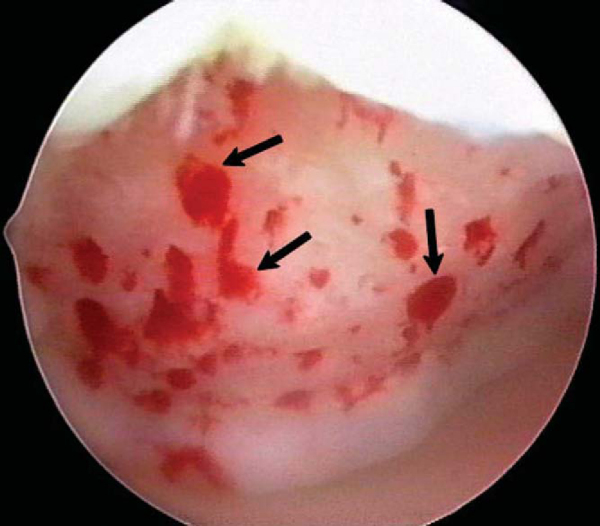

). After the arthroscopic irrigation fluid pump pressure is reduced, under direct visualization we are able to observe the flow of marrow fat droplets and blood from the microfracture holes into the prepared lesion (

Fig. 52-8

). The quantity of marrow contents flowing into the joint is judged to be adequate when we observe marrow elements emanating from all microfracture holes (

Fig. 52-9

). We then remove all instruments from the knee and evacuate the joint of fluid. [9] [10] [11] Intraarticular drains should not be used because the goal is for the surgically induced marrow clot rich in marrow elements to form and to stabilize while covering the lesion. [1] [2]